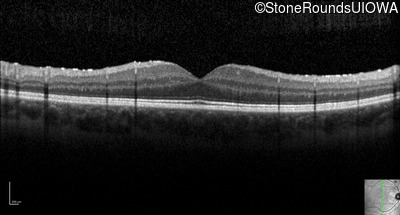

Optical Coherence Tomography - Right - 20/15 -1 sc

Exemplar / OCT Stack

OCT Stack

Optical Coherence Tomography - Left - 20/20 -1 sc